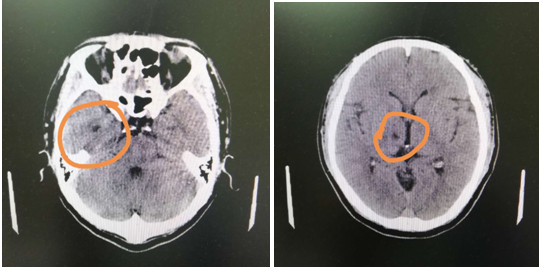

在徐主任的建議下,張師傅做了頭顱CT,檢查提示:兩基地節(jié)區(qū)、右側(cè)丘腦腔隙性腦梗塞,副鼻竇炎,腦干腔隙性梗塞不能排除。好在徐曉欣主任經(jīng)驗豐富,迅速聯(lián)系將張師傅轉(zhuǎn)入內(nèi)科,張師傅的腦梗得以及時治療。